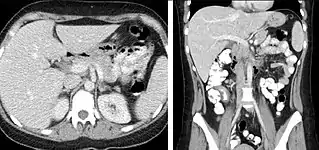

FIGURE 3. Axial (left) and coronal (right) CT angiography images of the abdominal aorta evaluating for aortic aneurysm.

CT angiography (CTA) is highly effective for evaluation of the arterial system, and has largely replaced conventional angiography due to the lower risk profile and ability to survey the entire abdomen. Images are acquired after a rapid bolus of intravenous contrast material (3-7 cc/s) during the arterial phase (15–35 seconds after injection) when the concentration of contrast material in the arterial system is high (figures 3). Images are usually acquired using narrow collimation (<1 mm) and can be retrospectively reconstructed using dedicated 3-dimensional workstations and software. CTA is commonly used in the head and chest in the evaluation of pulmonary emboli, aneurysms, vascular malformations, dissection, bleeding and ischemia. Indications for early arterial phase imaging include: evaluation of aneurysms or dissections (cerebral, aortic, etc.), hepatic, splanchnic or renal arterial anatomy, and arterial imaging in liver or kidney transplantation. Single phase arterial imaging is often used in the evaluation of trauma patients either a complete chest/abdomen/pelvis examination with arterial phase imaging of the chest and portal venous phase imaging of the abdomen/pelvis or just a portal venous phase of abdomen and pelvis depending on the mechanism and severity of the trauma. CTA is also commonly performed in the abdomen and pelvis for evaluating vascular malformations and in the evaluation of bleeding. Mesenteric ischemia can also be evaluated using CT angiography. CTA of the abdomen and pelvis is often performed in combination with a CTA for evaluating the extremity vasculature.